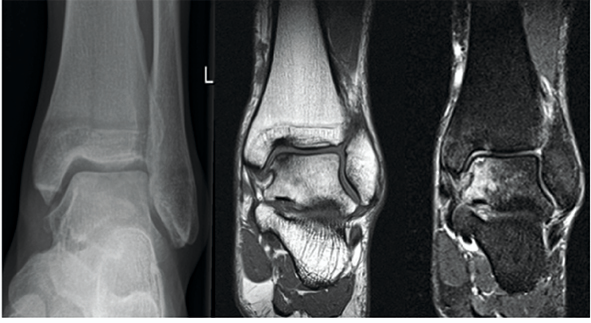

迟到一个月的踝关节骨折

图片尺寸912x684